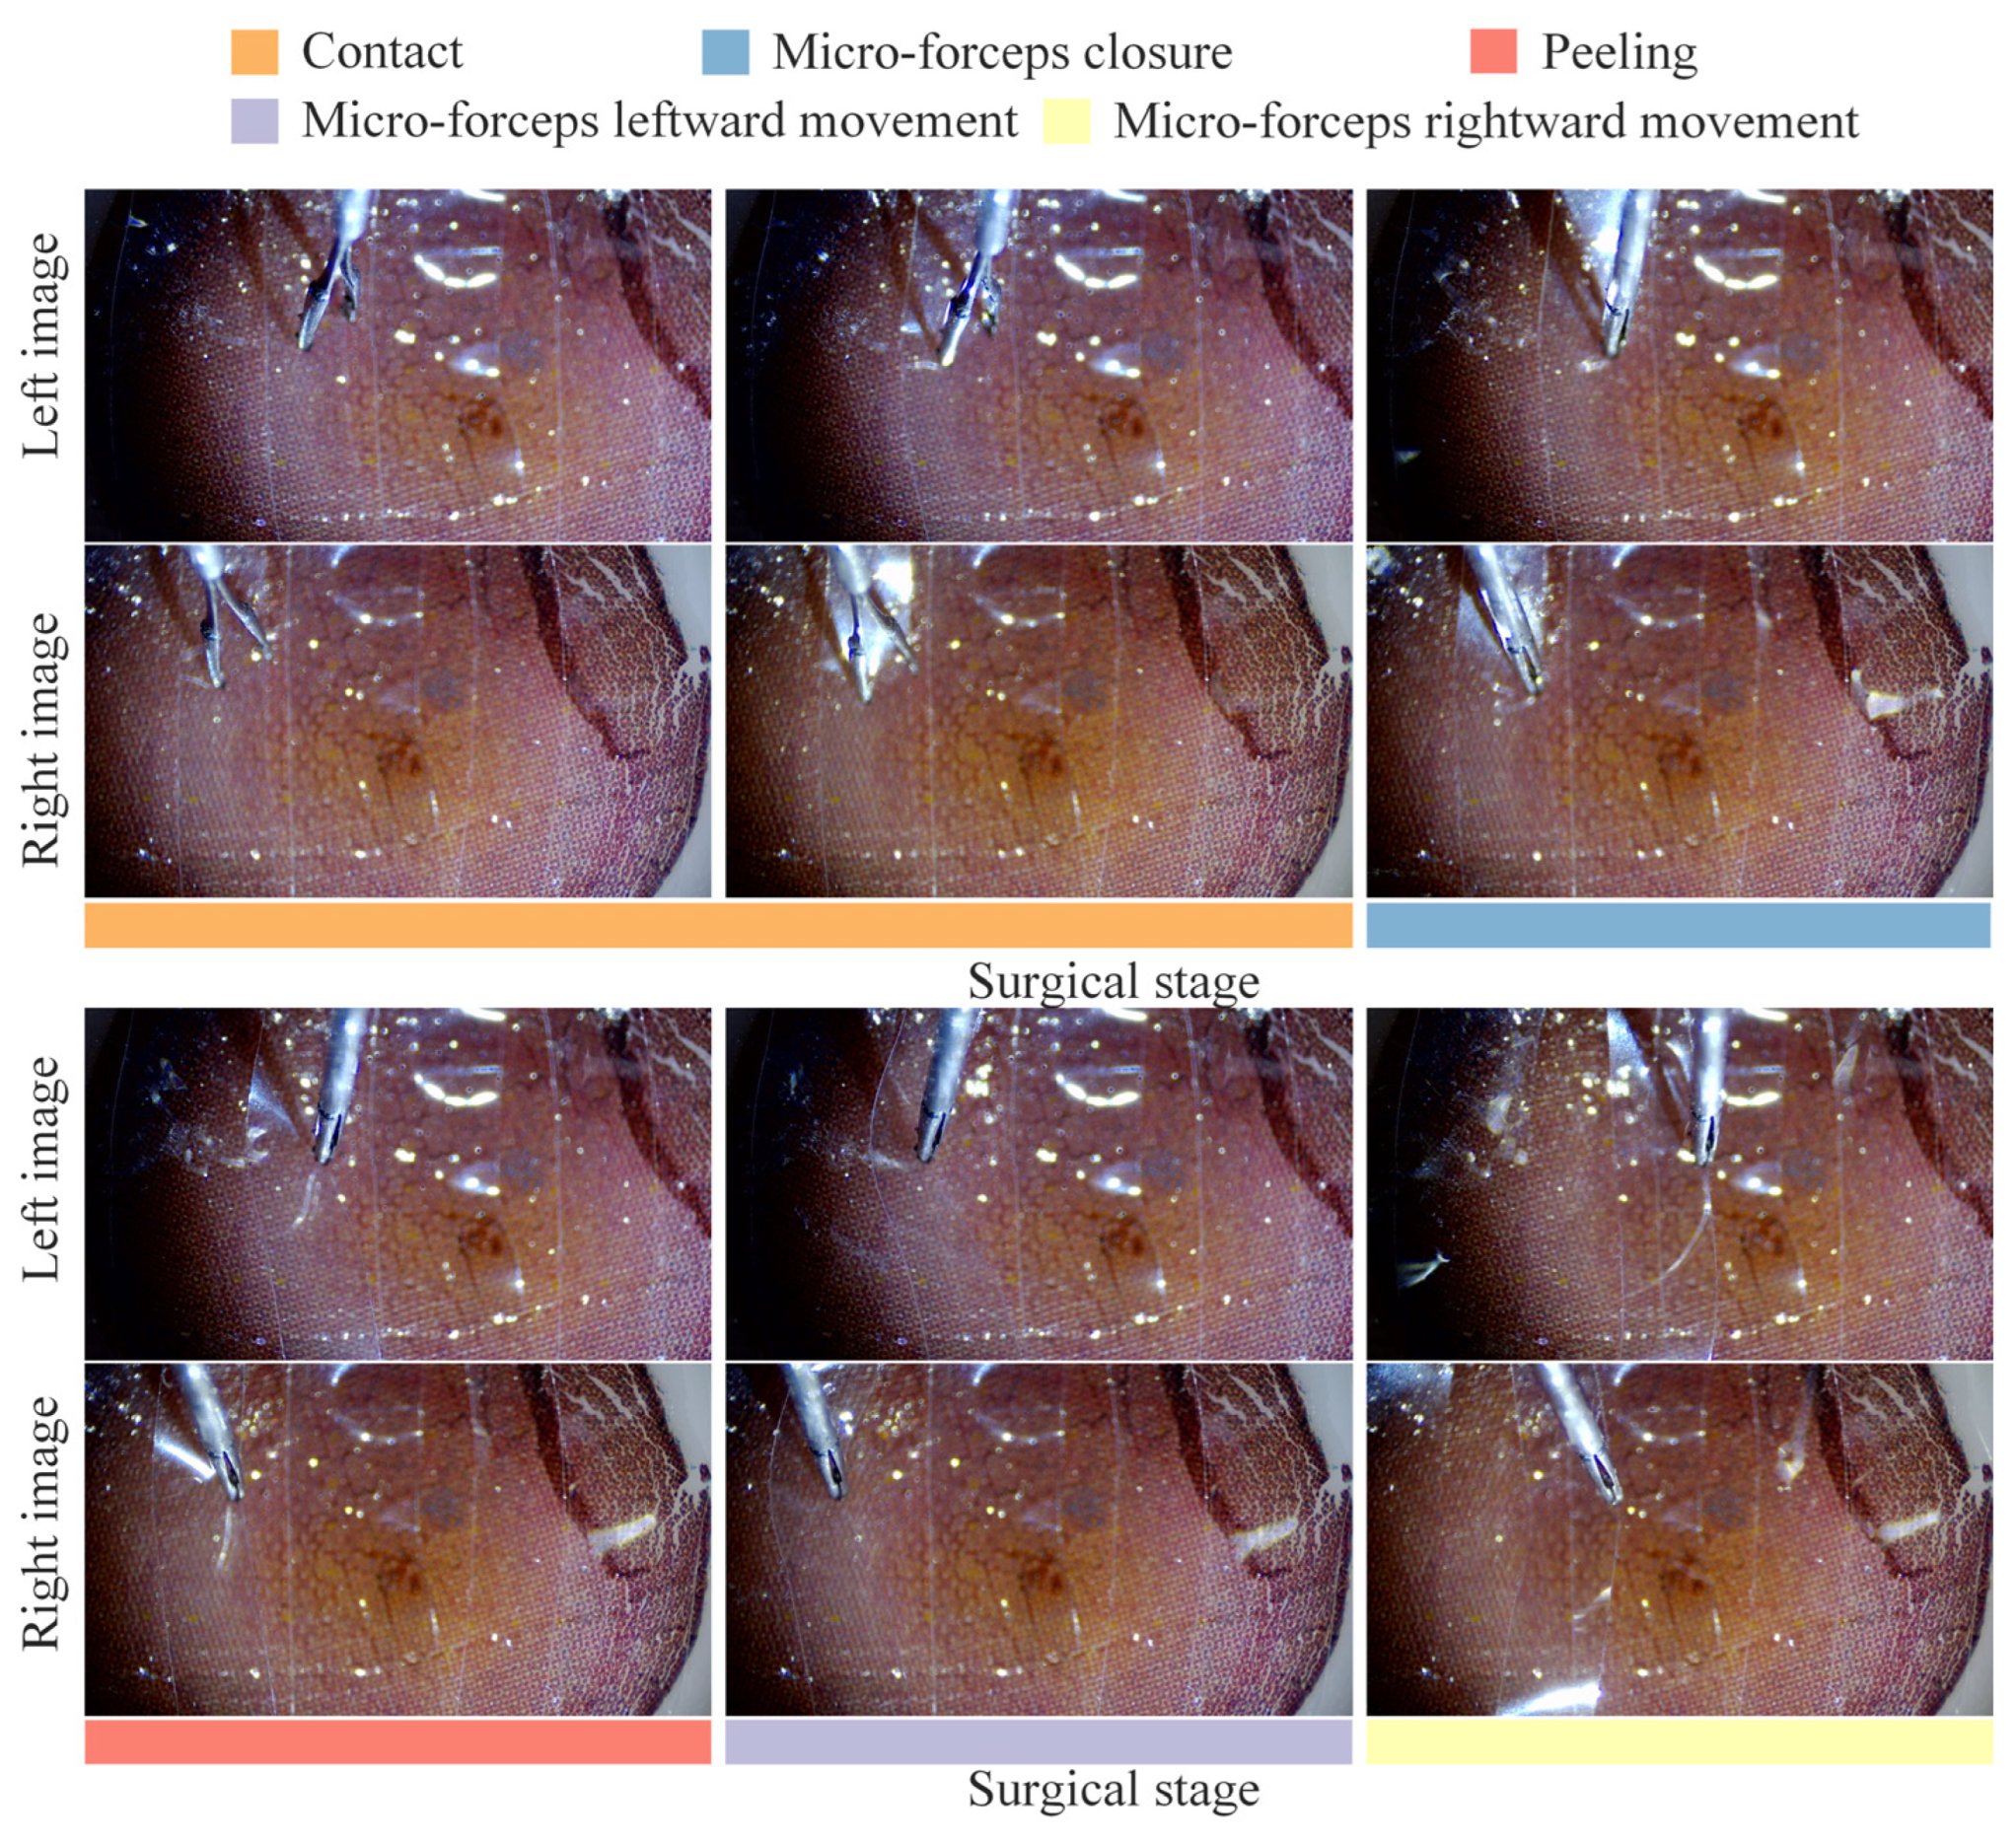

4.3. Break Initiation Experiment in ILM Peeling